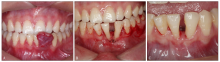

图 2

妊娠期龈炎的治疗1例A:初诊时;B:口腔卫生宣教后1周复诊;C:牙周基础治疗后1周复诊。"